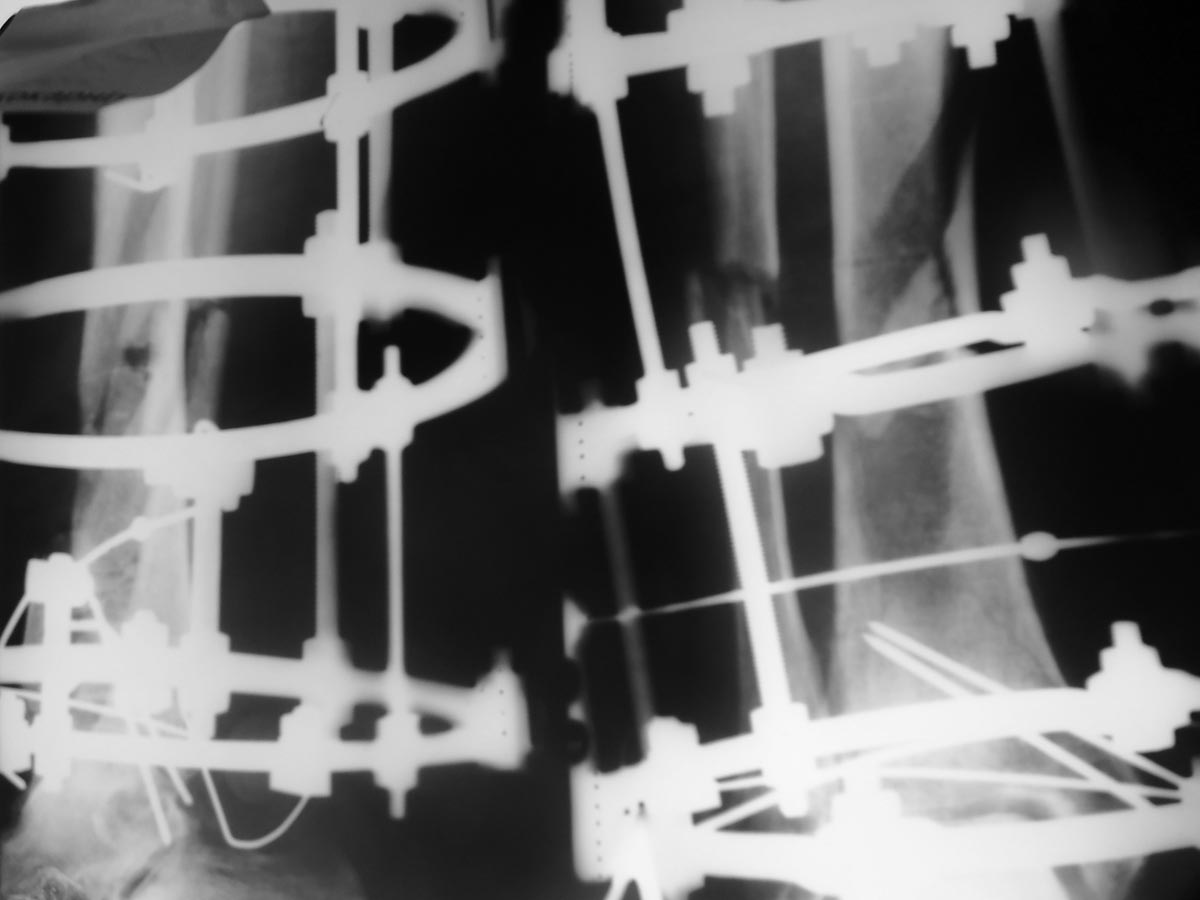

[Ortho] открытый перелом н/3 обеих костей левой глени

рентгенограммы

Вложение не в текстовом формате было извлечено…

Имя     : 100_0380[1].JPG

Тип     : image/jpg

Размер  : 81399 байтов